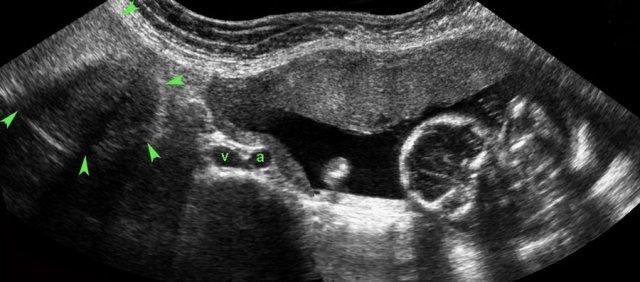

Ca lâm sàng 3

Bệnh nhân này được chuyển đến với nghi ngờ viêm ruột thừa có thủng.

Siêu âm cho thấy thai còn nguyên vẹn và ở phía phải tử cung (U.), một túi thai chứa thai nhi còn sống.

Tim thai được ghi nhận bằng siêu âm đầu dò âm đạo với chế độ M-mode (hình dưới bên phải).

Thai nhi còn sống được tìm thấy trong chưa đến 10% tổng số các trường hợp thai ngoài tử cung.